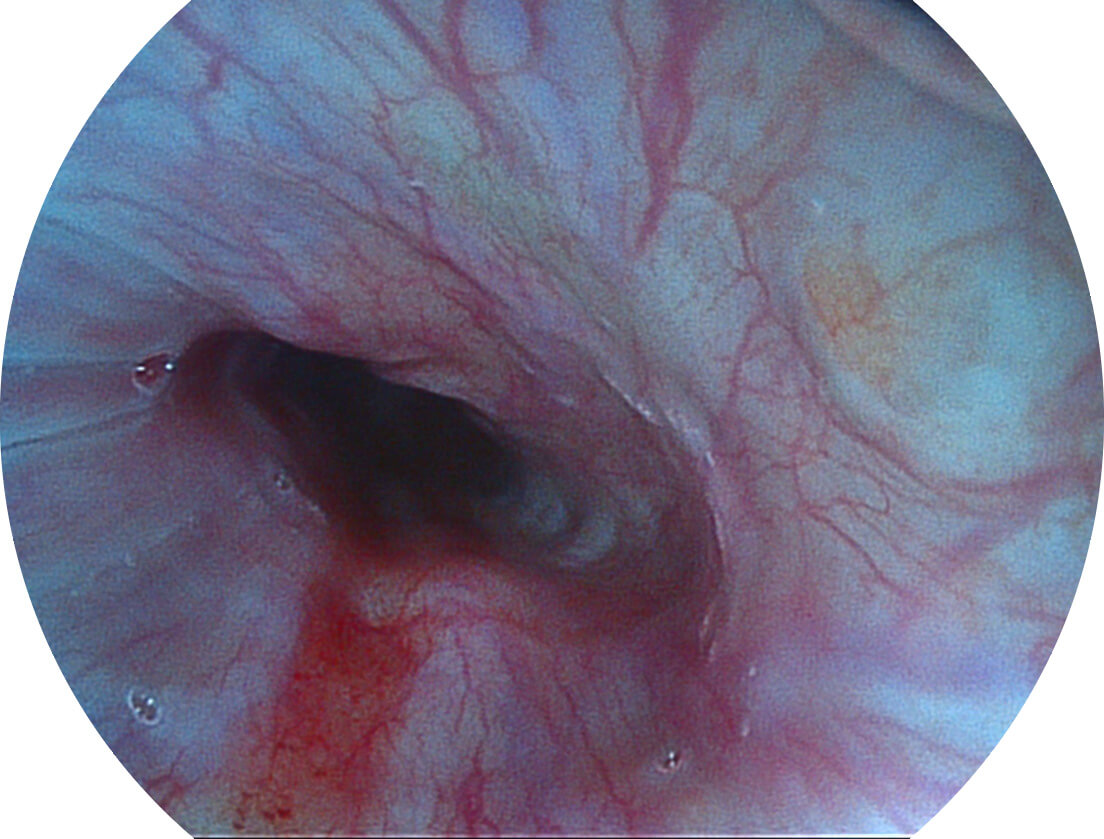

强调浅层黏膜结构的同时,保证照明亮度和提升浅层微血管与中层血管颜色对比度,病变边界更清晰。

白光图像